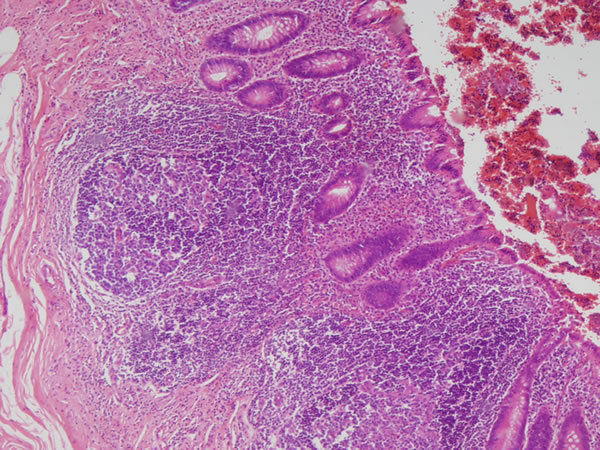

Linfonodo - tecido linfoide Necrose caseosa (parte rosinha no meio) - tuberculose ganglionar Causas: Histoplasmose, sarcoidose Outros achados: inflamação crônica (granuloma) |

Linfonodo -Tecido linfoide Necrose caseosa - tuberculose Outros achados: Infl. crônica - Granuloma epitelioide (rosinha, a parte roxa é normal) |

Linfonodo -Tecido linfoide Necrose caseosa (centro rosa)- tuberculose Outros achados: Infl. crônica - Granuloma epitelioide |

| Linfonodo -Tecido linfoide Necrose caseosa - tuberculose Outros achados: Infl. crônica - Granuloma epitelioide | |